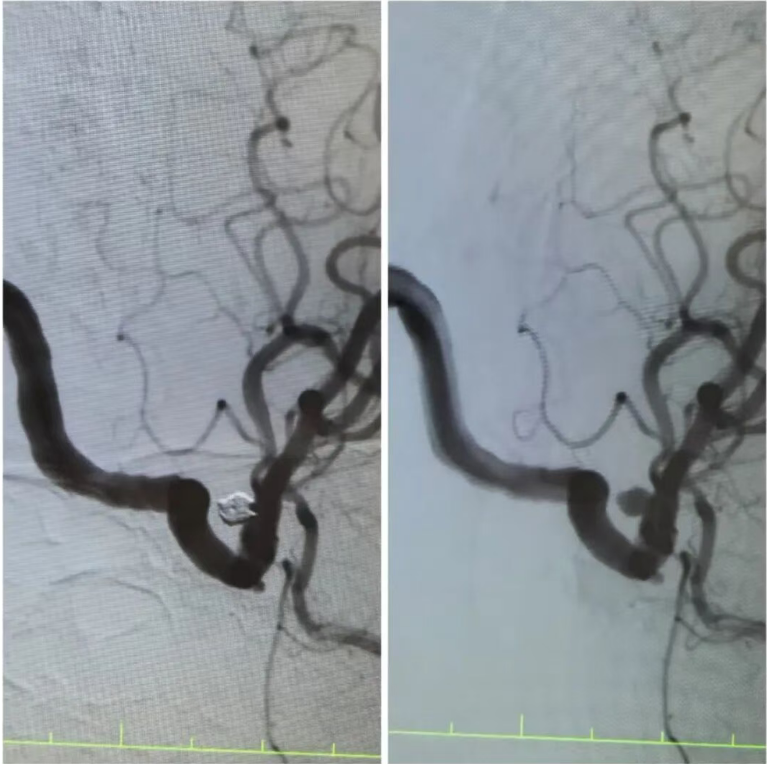

在王阿姨的造影檢查上,可清晰地看到動脈瘤的形態(tài):如同血管上懸掛的“小囊袋”,薄如蟬翼的瘤壁隨時可能再次破裂?!伴_顱手術(shù)創(chuàng)傷大,老人基礎(chǔ)疾病多,風(fēng)險極高,而介入栓塞術(shù),能通過股動脈穿刺的“鑰匙孔”路徑,精準封堵動脈瘤?!笔中g(shù)團隊反復(fù)推演方案,最終選定顱內(nèi)動脈瘤栓塞術(shù)——用纖細的微導(dǎo)管將彈簧圈送入動脈瘤腔內(nèi),像“織網(wǎng)”一樣填充瘤腔,隔絕血流沖擊,從根源上消除破裂風(fēng)險。

手術(shù)臺上,丁院長握著導(dǎo)管在血管中精準穿梭,如同在迷宮中尋找唯一的出口。當微彈簧圈依次填入動脈瘤,造影顯示瘤腔被完美“封堵”,載瘤動脈血流恢復(fù)通暢,這枚困擾老人許久的“炸彈”,終于被安全拆除。術(shù)后的王阿姨頭暈頭痛癥狀消失,胸悶氣短的老毛病也因身心狀態(tài)改善而減輕。“感覺腦袋里的‘炸彈’沒了,整個人都輕快了!”